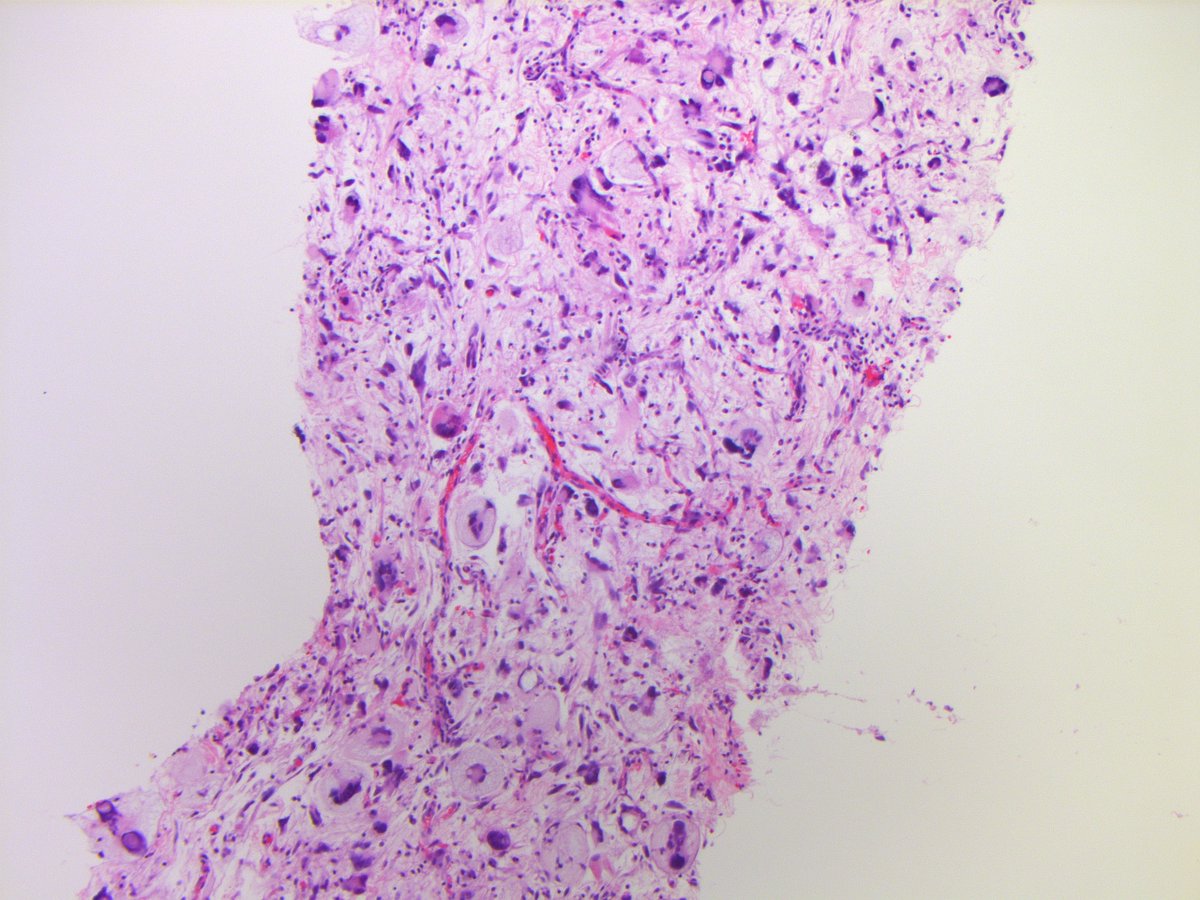

Epithelioid-spindle cells arranged in sheets-fascicles. Abundant amphophilic cytoplasm. Round-ovoid nuclei with pleomorphism, macronucleoli & brisk mitotic activity. Interspersed neutrophils. Necrosis is conspicuous. A basic spindle cell panel was non-contributory. DDx:

In this neoplasm IHC was diffusely positive for MDM2 and CDK4, and FISH confirmed the presence of MDM2 amplification. The findings support classification as DEDIFFERENTIATED LIPOSARCOMA (epithelioid variant). PMID: 28719466, 29307627.